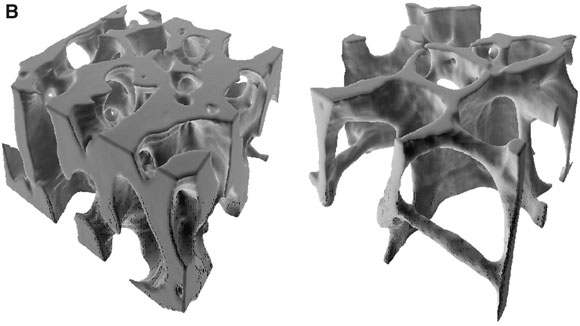

2: Bone in osteoporosis

B. Loss of trabeculae and thinning (right) reduce cross-sectional area so that loads on bone are relatively greater (reprinted from Keaveny et al 8 with permission from Annual Review of Biomedical Engineering [www.annual.reviews.org]).